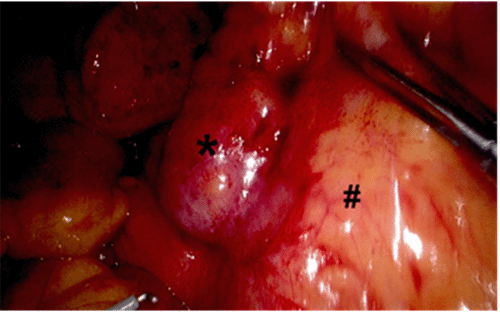

Our patient initially presented to the emergency department (ED) on day one of her symptoms; however, the pain was reported in the epigastric region at that stage. She was discharged home after further clinical work-up with normal bloods and upper abdominal ultrasound. The pain, however, persisted and began radiating to the RLQ. She saw her primary practitioner, who ordered a computed tomography (CT) scan of the abdomen and pelvis, which demonstrated marked thickening of a dilated distal appendix measuring 1.6 cm and associated surrounding fat stranding (Figure 1 and Figure 2). After receiving these findings, she was advised to re-present to our ED for further clinical review.

Figure 1. CT Coronal Slice, Demonstrating Thickened Dilated Appendix (arrow). Published with Permission